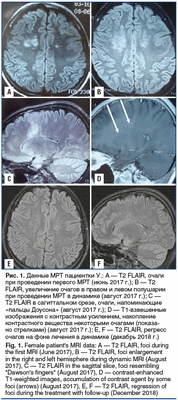

Пациентка У., 31 год, заболела в июне 2017 г., когда возникли диффузные, распирающие, труднопереносимые головные боли, не купируемые анальгетиками, усиливающиеся при малейшем движении головой. Головная боль сопровождалась тошнотой, рвотой. В течение недели боль нарастала: больная перестала заниматься повседневными обычными делами, постоянно лежала, продуктивный контакт был ограничен. Повышения температуры или других признаков инфекционного заболевания не наблюдалось. К концу недели стало беспокоить двоение при взгляде на любые расстояния. Движения глазных яблок сопровождались болью. Появились шаткость при ходьбе, неустойчивость, дрожание в руках. Утратила возможность передвигаться без поддержки. Проконсультирована окулистом, который обнаружил выраженные застойные явления на глазном дне и рекомендовал проведение магнитно-резонансной томографии (МРТ) головного мозга с последующей консультацией невролога. На МРТ головного мозга выявлен «конгломерат» множественных очагов в правой и, меньших размеров, на симметричном участке в левой лобно-теменной области (рис. 1, А).

В неврологическом статусе при поступлении описаны равномерное оживление глубоких рефлексов, мозжечковая походка, выполнение координаторных проб с интенцией, неустойчивость в позе Ромберга. К сожалению, в выписке из истории болезни не отражено наличие головной боли, нет описания общего статуса пациентки. Выставлен диагноз «рассеянный склероз (РС)». Получала терапию глюкокортикостероидами, на фоне которой регрессировали головные боли, застойные явления на глазном дне; продолжали беспокоить общая слабость, дрожание в кистях. На МРТ головного мозга, проведенной через 2 мес. после первого обследования, констатировали появление новых очагов, увеличение площади поражения; очаги напоминающие «пальцы Доусона», накопление контрастного вещества некоторыми очагами (рис. 1, B-D). Для исключения системных заболеваний соединительной ткани (СЗСТ) больная прошла обследование в ФГБНУ НИИР им. В.А. Насоновой. Общий анализ крови, скорость оседания эритроцитов, антитела к двуспиральной ДНК, антитела к кардиолипинам IgG, IgM, С3- и С4-компоненты комплемента, ANCA, антинуклеарный фактор — все параметры в пределах нормы, на основании чего СЗСТ исключены. Пациентка была обследована в одной из клиник г. Москвы, диагноз РС подтвержден. Там же проведена МРТ спинного мозга — патологии не обнаружено.

Стандартное лабораторно-инструментальное обследование пациентки (биохимический анализ крови, электрокардиография, рентгенография органов грудной клетки, ультразвуковое исследование сосудов шеи) патологии не выявило. Осмотр офтальмолога: состояние глазного дна — диск бледно-розовый, границы четкие, калибр сосудов не изменен. МР-веносинусография и КТ-ангиография с венозной фазой: крупные вены и синусы не изменены, за исключением умеренного расширения корковых вен среднего и дистального сегмента справа (на уровне верхней анастоматической вены Тролярда) (рис. 2), что может служить признаком формирования коллатерального оттока.

По согласованию с гематологом назначен варфарин с коррекцией дозы в соответствии с цифрами международного нормализованного соотношения. На контрольной МРТ отмечается значительный регресс очагов (рис. 1, E, F). На фоне антикоагулянтной терапии пациентка смогла забеременеть и родить здорового ребенка. Рецидивов заболевания в течение 2 лет наблюдения не было, сохранялся описанный выше неврологический дефицит.

ткани [16]. Идентичность очагов при CLIPPERS с очагами нашей больной позволяют расценивать их как сосудистые. Наличие перифокального отека свидетельствует о вовлечении в процесс мелких вен. Подтверждением сказанного является формирование венозных коллатералей (см. рис. 2), локализация очагов в обоих полушариях головного мозга, симметричность их расположения, клиническая картина и, наконец, сама причина заболевания — тромбофилия.